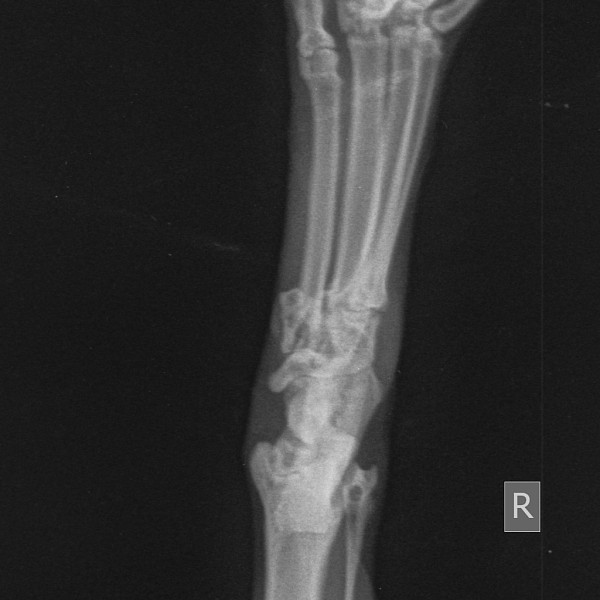

Здравствуйте. У кота, 3 года, несколько дней назад появилась кровоточащая рана в области скакательного сустава на задней конечности, кот не хромает. На улице не бывает, вероятность что поранился маленькая. Неделю назад заболел кальцивирозом, делали инъекции циклоферон внутримышечно, сейчас ничего не принимает. Повязку упорно разлизывает, то есть рана либо зудит, либо болит. Вет врач точного заключения сделать не смог, назначил антибиотики и обезболивающее, предположил что это психогенное разлизывание и имеется вывих. Подскажите пожалуйста мог ли кот вывихнуть лапу или это последствия болезни или лечения от кальцивироза?

Состояние на данный момент